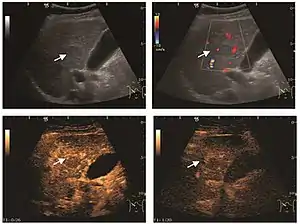

It is the most common liver tumor with a prevalence of 0.4 – 7.4%. It is generally asymptomatic but also can be associated with pain complaints or cytopenia and/or anemia when it is very bulky. It is unique or paucilocular. It can be associated with other types of benign liver tumors. Characteristic 2D ultrasound appearance is that of a very well defined lesion, with sizes of 2–3 cm or less, showing increased echogenity and, when located in contact with the diaphragm, a "mirror image" phenomenon can be seen. When palpating the liver with the transducer the hemangioma is compressible sending reverberations backwards. Doppler exploration reveals no circulatory signal due to very slow flow speed. CEUS investigation has real diagnosis value due to the typical behavior of progressive CA enhancement of the tumor from the periphery towards the center. The enhancement is slow, during several minutes, depending on the size of hemangioma and on the presence (or absence) of internal thrombosis. During late (sinusoidal) phase, if totally "filled" with CA, hemangioma appears isoechoic to the liver. Deviations from the above described behavior can occur in arterialized hemangiomas or those containing arterio-venous shunts. In these cases, differentiation from a malignant tumor is difficult and requires other imaging procedures, follow up and measurements of the tumor at short time intervals.[4]

Focal nodular hyperplasia